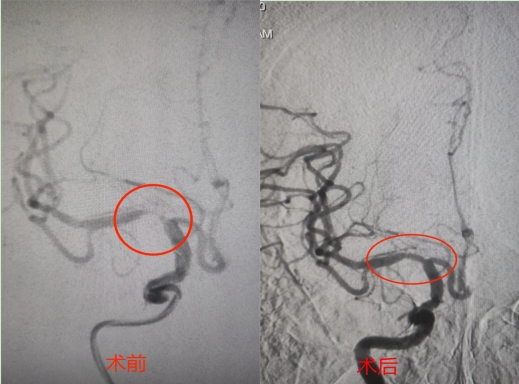

术前术后对比。

7月22日上午,在完善相关术前检查后,吴老先生被推进介入导管室,在朱灿敏主任神经内科团队的默契配合下,用时一个半小时,在吴老先生右手腕桡动脉处开通介入通路,通过大脑中动脉血管形成术,顺利完成了该院首例经桡动脉入路的大脑中动脉血管形成术。术中吴老先生生命体征平稳,仅有造口处极少量出血,术后恢复良好,双侧肢体肌张力恢复正常,下地行走如常,吐词清晰,预计本周可以康复出院。

“入院后,行脑血管造影、磁共振灌注成像,证实脑血管狭窄,脑组织缺血。”江夏区第一人民医院神经内科朱灿敏通过影像检查结果,排除“脑梗死”诊断,并及时与吴老先生沟通下一步治疗方案。